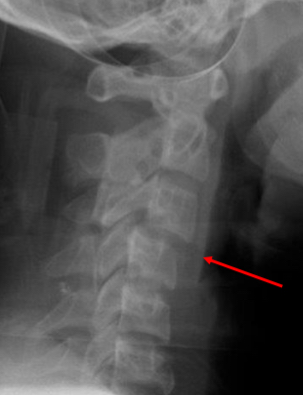

describe this radiograph

Anterior soft tissue measuring more

than 20mm at the level of C6.

• Indicates possible trauma.

• Patient has a tear-drop fracture of the

vertebral body of C3